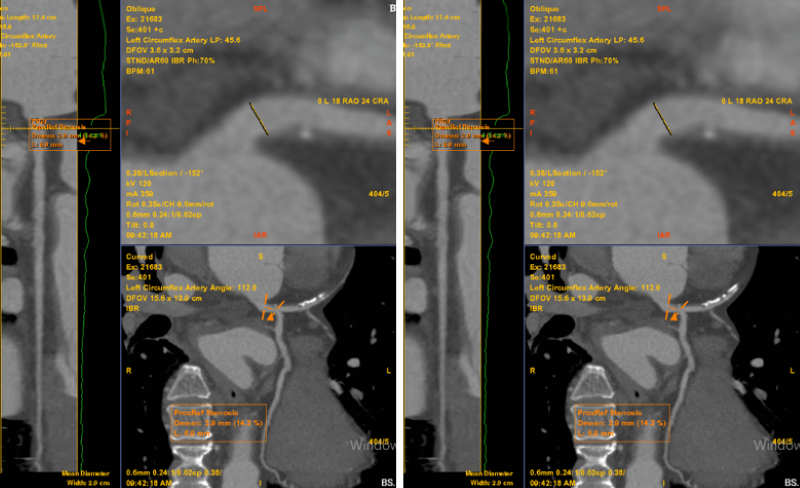

Kết quả phát hiện mảng xơ vữa hỗn hợp gây hẹp khoảng 60 - 70% đoạn LAD1–2, được phân loại CAD-RADS 3. Chẩn đoán xác định, bệnh nhân mắc bệnh mạch vành mạn tính do vữa xơ. Bác sĩ tiến hành lên phác đồ điều trị nội khoa, bao gồm kiểm soát chặt chẽ các yếu tố nguy cơ tim mạch và điều trị dự phòng biến cố. Hiện tại, bệnh nhân tiếp tục duy trì điều trị nội khoa theo phác đồ, tình trạng sức khỏe ổn định, không còn ghi nhận triệu chứng đau ngực hay khó thở.

Bất thường được phát hiện trên phim chụp MSCT mạch vành của bệnh nhân